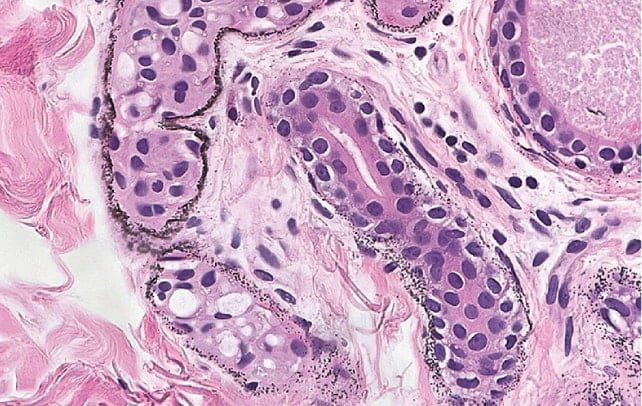

Arjiri, gümüşün ter bezleri, kan damarları ve deri liflerinde oksitlenerek küçük granüller halinde birikmesi sonucu cildin mat gri bir ton almasına neden olan bir hastalıktır. Genellikle, gümüş madenlerinde çalışanlar veya gümüş içeren ilaçları uzun süre kullanan bireylerde görülmektedir. Ancak, bu 84 yaşındaki hasta, geçmişinde böyle bir maruziyet olmadığını belirtmiştir. Yıllarca garson olarak görev yapan adamın iş yerinde veya ev ortamında gümüşle temas etme olasılığı da araştırmalar sonucunda bulunamamıştır.

Gümüş, genellikle solunum, cilt veya sindirim sistemi yoluyla vücuda girmektedir. Vücutta dolaşan bu metal, güneş ışığına maruz kaldığında gri veya mavi tonlar oluşturan kimyasal reaksiyonlara yol açmaktadır. Neyse ki, arjiri çoğu durumda ciddi sağlık sorunlarına neden olmamaktadır. Ancak, yüksek gümüş birikimleri bazı ilaçların emilimini engelleyebilir.